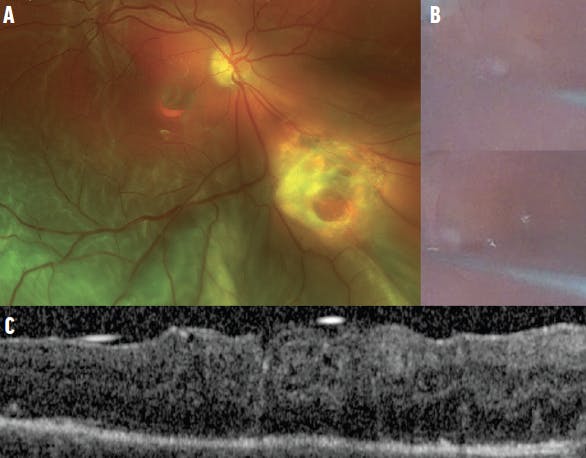

In our experience, delayed detachments occurring weeks after an ART are not associated with a dislocation, as the graft is already integrated within the retina; thus, the surgeon can focus on fixing the detachment. However, a delayed PVR detachment with graft displacement can occur (Figure 4). Once PFCL is injected to reposit the ART, the retina can be successfully attached with excellent stability of the ART.

Figure 4. The fundus photograph shows a post-ART PVR detachment with a dislodged ART that is only partially closing the MH (A). The intraoperative photographs demonstrate the use of PFCL to reposit the ART (B). The postoperative OCT shows excellent ART placement (C).